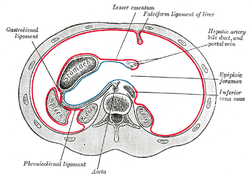

The celiac artery and its branch. Horizontal disposition of the peritoneum in the upper part of the abdomen.

Horizontal disposition of the peritoneum in the upper part of the abdomen. Transverse section of the spleen, showing the trabecular tissue and the splenic vein and its tributaries.